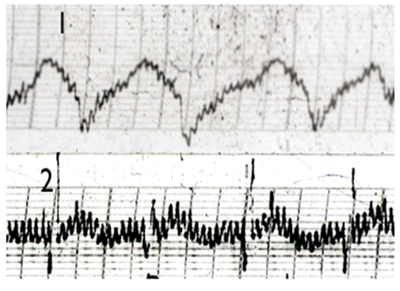

3. The waveform of the electrogram readings of SHU points was modified when their associated organs were diseased. In patients with confirmed gastric ulcer, the waveform of the electrogram reading of the stomach SHU point (BL 21) was modified, while electrogram readings of other SHU points were similar to those of healthy subjects (Figures 2,3). Similarly, in patients with cardiac arrhythmias, the waveform of the electrogram reading of the heart SHU point (BL 15) was modified, while readings of other SHU points were similar to those of healthy subjects.

4. The abnormal presentation of the electrogram reading of the stomach SHU point (BL21) associated with gastric ulcer disease consisted of a large number of fast, high amplitude discharges (Figure 3).

5. The abnormal activity in the electrogram reading of the heart SHU point (BL 15), associated with cardiac arrhythmias, also consisted of a large number of fast, high amplitude discharges (Figure 4).

Figure 2 patient with stomack ulcer. EG trace of 1. Stomack SHU point (BL21); 2. Sham(non-active point) and 3. Heart SHU point (B115).

Figure 3 EG trace of Stomack SHU acupuncture points (BL21): 1. Heart SGU point; 2. Patient with confirmed Stomach ulcer.

Figure 4 EG trace of Heart SHU acupuncture points (BL 15): 1. Healthy person; 2. Patient with cardiac arrhythmias.